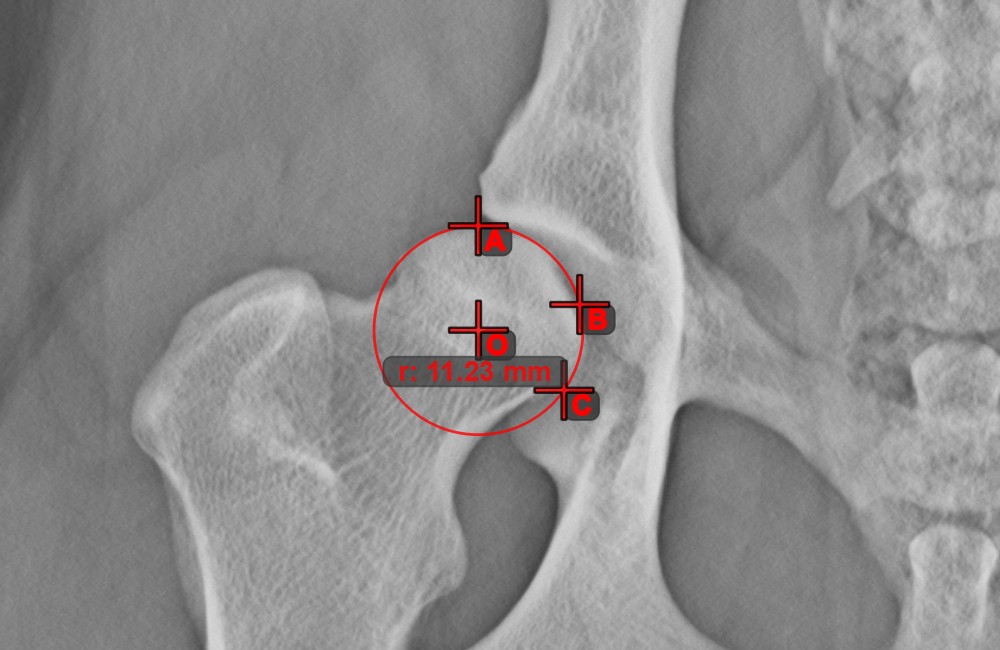

Kreis aus 3 Punkten¶

Das Werkzeug Kreis aus 3 Punkten ist eine einfache und effektive Möglichkeit, einen Kreis anhand von nur drei Punkten zu erstellen.

Beginnen Sie, indem Sie das Werkzeug aus der linken Symbolleiste auswählen und einer der verfügbaren Maustasten zuweisen. Setzen Sie die drei Punkte des Kreises oder wählen Sie die Punkte aus den in der Szene verfügbaren aus. Der Kreis wird automatisch basierend auf der Position der drei Punkte erstellt. Der Ursprung des Kreises wird stets mit O markiert. Der Radius des Kreises wird automatisch berechnet.

Ändern Sie die Position der drei Punkte, um den Radius des Kreises mit dem Werkzeug Objekt auswählen/verschieben zu ändern.